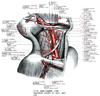

A12_2_08_043

下甲状腺動脈Inferior thyroid artery(Arteria thyroidea inferior)

下甲状腺動脈【かこうじょうせんどうみゃく】 Artery passing along the anterior border of the anterior scalene muscle to the level of the sixth cervical vertebra and then behind the common carotid artery to the thyroid gland.(下甲状腺動脈は沿う頚動脈の後方を内側へ走り、甲状腺下部にいたる。甲状腺に分布する腺枝のほかに、周囲気管への分枝として下喉頭動脈、咽頭枝、食道枝、気管枝を分岐する。)